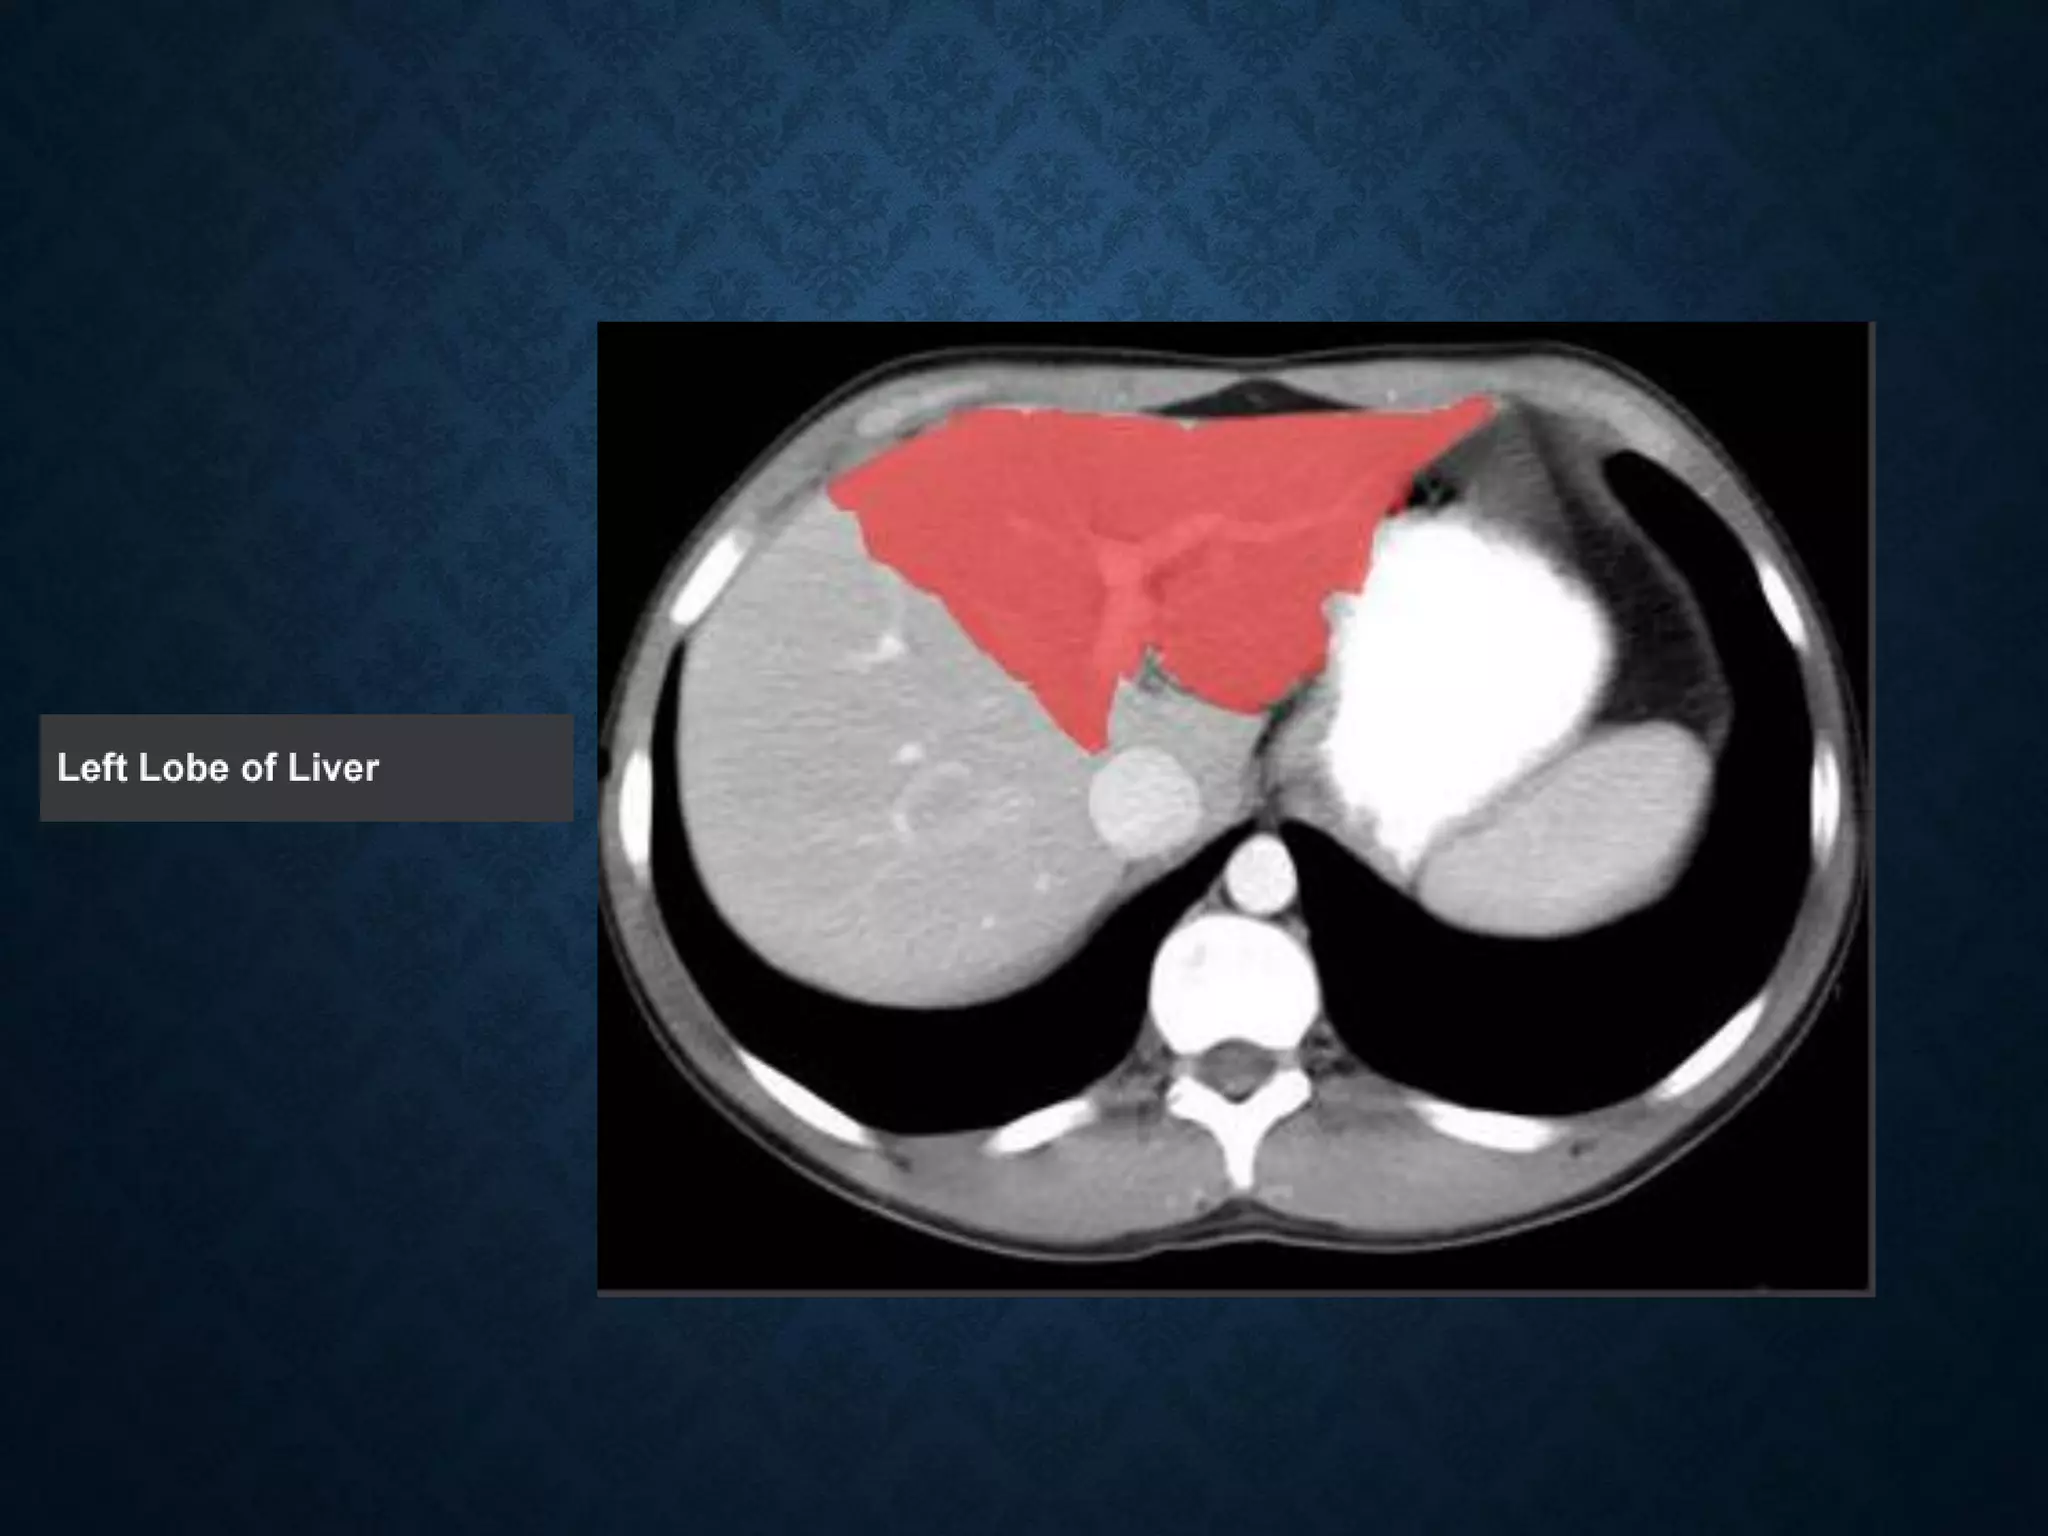

Identify the following structures in the body CT to the right. To view the location of the structure in the image click on

the label at the left and the structure will be indicated in the image. Abdominal CT scans typically begin just above

the diaphragm, so the first slice you see is of the lower chest.

Identify the followingstructures in the body CT to the right. To view the location of the structure in the image click on the label at the left and the structure will be indicated in the image. Abdominal CT scans typically begin just above the diaphragm, so the first slice you see is of the lower chest.